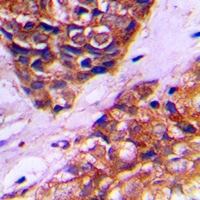

Immunohistochemical analysis of PEX10 staining in human prostate cancer formalin fixed paraffin embedded tissue section. The section was pre-treated using heat mediated antigen retrieval with sodium citrate buffer (pH 6.0). The section was then incubated with the antibody at room temperature and detected using an HRP conjugated compact polymer system. DAB was used as the chromogen. The section was then counterstained with haematoxylin and mounted with DPX.